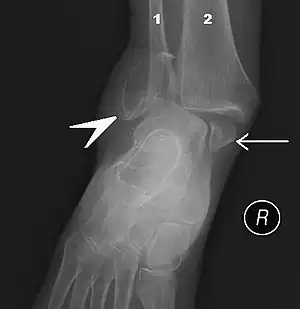

The initial evaluation of suspected ankle pathology is usually by projectional radiography ("X-ray").

For ligamentous injury, there are three main landmarks on X-rays: The first is the tibiofibular clear space, the horizontal distance from the lateral border of the posterior tibial malleolus to the medial border of the fibula, with greater than 5 mm being abnormal. The second is tibiofibular overlap, the horizontal distance between the medial border of the fibula and the lateral border of the anterior tibial prominence, with less than 10 mm being abnormal. The final measurement is the medial clear space, the distance between the lateral aspect of the medial malleolus and the medial border of the talus at the level of the talar dome, with a measurement greater than 4 mm being abnormal. Loss of any of these normal anatomic spaces can indirectly reflect ligamentous injury or occult fracture, and can be followed by MRI or CT.[26]